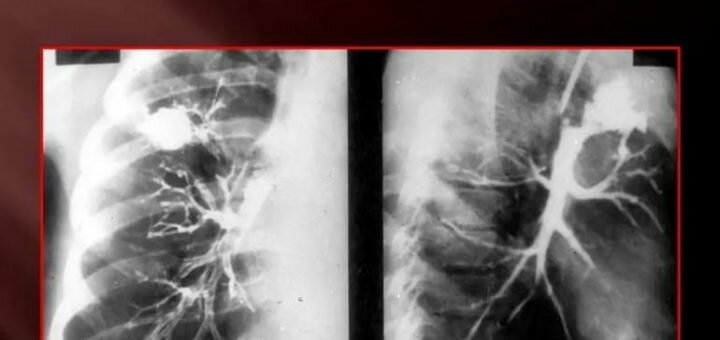

Протекание воспалительного процесса характерно для организма человека в любом возрасте. Воспаление бывает разное. Особое внимание врачи уделяют воспалительным процессам органов дыхания. Наши дыхательные пути подвержены большому количеству инфекций. Многие инфекции, бактерии поражают верхние дыхательные,...